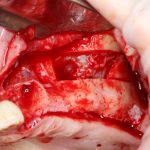

Для получения костного блока, мы открываем донорскую зону, наружную косую линию нижней челюсти.

Получение костного аутотрансплантата.

Здесь потребуется пародонтологический зонд с миллиметровой разметкой или какой-то другой измерительный прибор (операционная линейка). Ранее по КЛКТ я измерил костный дефект, теперь нужно нанести границы будущего костного блока на донорскую зону.

Для получения костного блока мы использовали ультразвуковую пьезохирургическую систему. Это самый удобный и безопасный инструмент для проведения подобных манипуляций. С помощью него мы сформировали и выделили костный блок. Он должен отделяться легким движением остеотома или элеватора. Как это сделать правильно — читай здесь>>